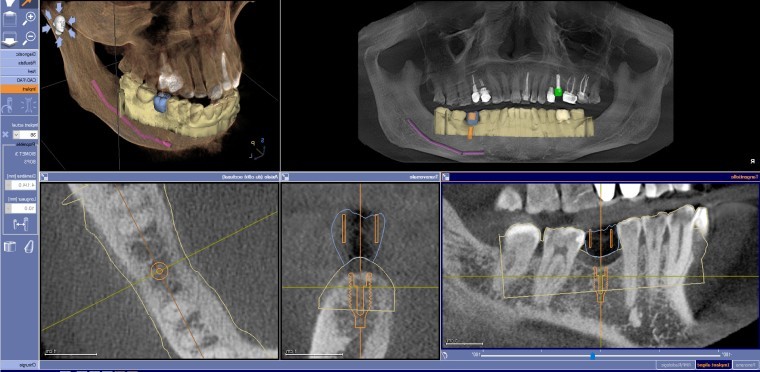

Cone Beam Dentaire à Toulouse : avantages de la modélisation 3D